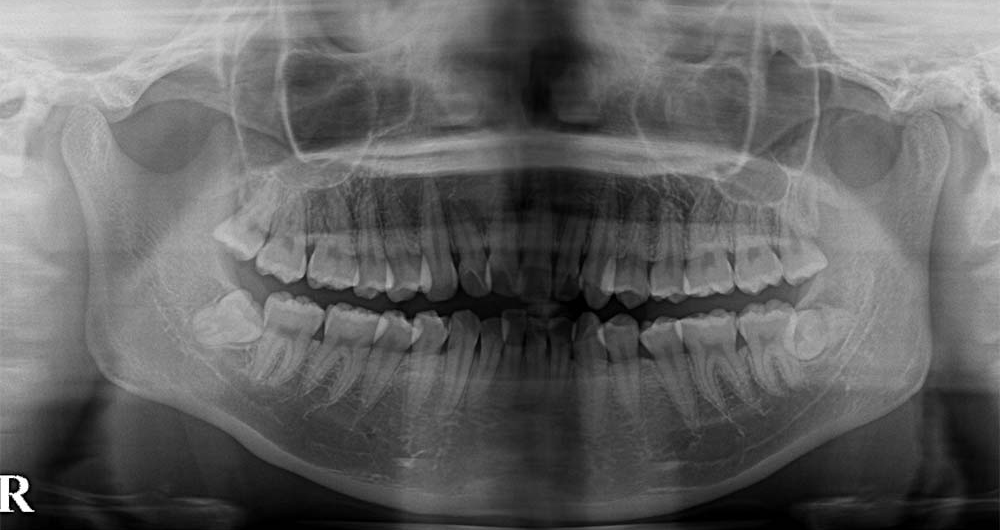

20代男性

ケース2:右下に食べ物がつまる

矯正治療中の患者さんですが、県内の歯科医院より紹介頂き受診されました。初診の当日に処置を行っています。

神経と歯の根が近かったためCTにて位置関係を3次元的に確認したうえで、5mm程度の切開を行い歯の頭の部分を削って抜きました。2糸縫って終わっています。

術後は紹介先で経過を診て頂いていますが、少しの腫れはあったようですが痺れ等はなかったようです。

- 所要時間

- 15分程度

- 費用

- ¥9,000(健康保険内)